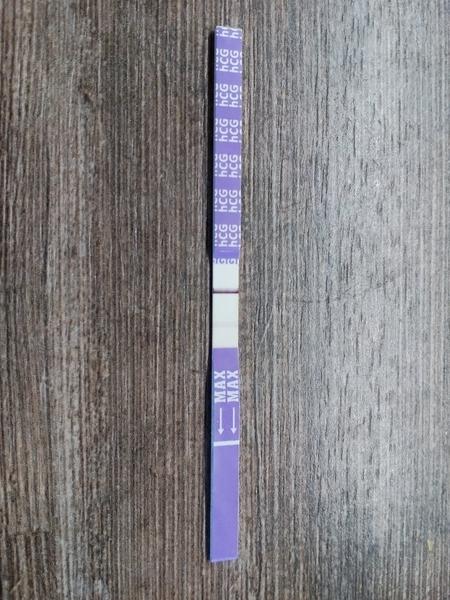

Takhle mi to začínalo, potom jsem si dělal test, když jsem těhotenství mela potvrzené od doktorky a čárky už byly krásné :D

Tak jsem si vcera delala ten digital, a pry jsem tehu, udajne 2-3tyden, pecka, mame hroznou radost, snad ne predcasnou. Doufam ze se vyklindim protoze se porad neceho obavam 😂 meli jste tomi nekdo take tak?jo a stale mi boli jakoby vajecniky, je to normalni? Diky pa

@baruskawh delala jsem si ten digi, ten vysel pozitivne, tak ve stredu jdu k doktoru tak snad tam bude broucek 😇